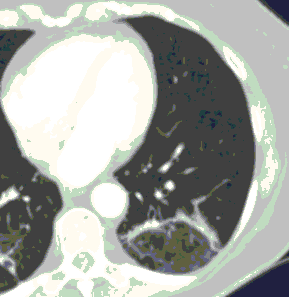

6. Внутривенное контрастирование при КТ у пациентов с известной/предполагаемой вирусной (COVID-19) пневмонией проводится при подозрении на заболевания и патологические состояния, диагностика которых невозможна без использования контрастных средств (ТЭЛА, онкологические заболевания др.). Внезапный рост концентрации Д-димера в анализах крови и клиническое подозрение на ТЭЛА являются важными критериями для выполнения КТ-ангиопульмонографии при условии, что ее положительный результат может оказать влияние на лечение и ведение пациента.

7. Решение о внутривенном контрастировании принимает врач-рентгенолог совместно с врачом, направляющим пациента на КТ. Введение контрастного средства выполняется в соответствии с общими правилами проведения рентгеноконтрастных исследований.